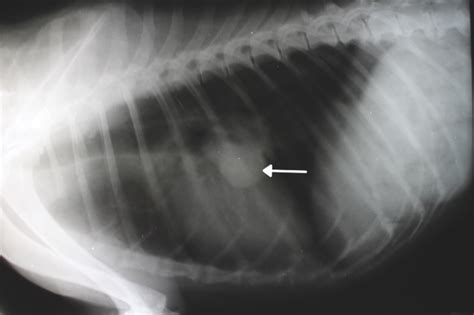

Thoracic (chest) radiographs are the most important tool in diagnosing this condition in pets. After diagnosis your dog may be referred to a veterinary oncologist for treatment. See full list on petmd.com Nov 13, 2017 · on top of dogs presenting symptoms derived from the primary tumor, in advanced cases, dogs will also show signs of lung cancer. For ongoing treatment, you may need to visit your veterinary oncologist on a regular basis. Chronic cough no appetite weight loss exercise intolerance coughing blood bloody urine or stool constant sneezing difficulty breathing rapid breathing shortness of breath extreme lethargy and/or. Justanswer.com has been visited by 100k+ users in the past month Many chemotherapeutic agents can be hazardous to your health if not handled properly, consult with your veterinarian regarding the best handling practices. During this period you can improve your dog's quality of life by providing extra comfort and affection. Symptoms of lung cancer in dogs in the absence of diagnostic testing, it can be challenging to detect lung cancer in dogs. Check poison symptoms, diagnosis & treatments. See full list on petmd.com The ct scan and mri may also help in determining the possibility of metastasis of the tumor into other parts of the body.

Lameness, in cases with metastasis to bones 9. Surgery will usually be chosen for removing a well localized tumor in the lungs and resection of the affected lung lobe. Thoracic (chest) radiographs are the most important tool in diagnosing this condition in pets. Get nhv's most useful pet cancer supplements in one holistic pack! See full list on petmd.com Help your pet cope with symptoms like nausea, loss of appetite and energy. Get nhv's most useful pet cancer supplements in one holistic pack! Most symptoms are related to the respiratory system, but in cases of metastasis the symptoms may vary depending upon the location of the metastasis in the body. Check poison symptoms, diagnosis & treatments. No single treatment works for all patients. Chemotherapy and radiotherapy are often used in combination to improve the prognosis and to increase the survival period. Justanswer.com has been visited by 100k+ users in the past month Jan 29, 2021 · metastatic lung tumors are tumors that originate from cancer elsewhere in the dog's body then spread to the lungs.